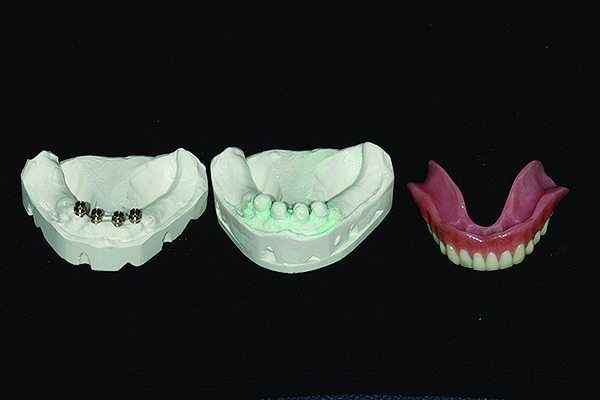

Impressions were beaded, boxed, and poured. Subsequent models were mounted on semi-adjustable articulator prior to separation. This ensures a totally accurate transfer of occlusal relationships prior to any possible distortion resulting from separation of the models. The facebow transfer and new bite registration records were used. Laboratory putty matrices were taken of the incisal edge position of the maxillary anterior region. Clear dentures were separated from models and retained for future reference. Stabilized baseplates were developed and a new wax set up was created using the existing maxillary incisal edge position and a completely new centric relation position. Lower anterior teeth were placed in appropriate position relative to the edentulous ridge and fully balanced occlusion was developed using a 20° semi anatomic denture tooth on the maxillary and a 0° tooth on the mandibular. The completed wax setup was returned for clinical evaluation and patient approval.

Retentive abutments were simulated on the master mandibular cast following cone beam confirmation of locations. Clearance was waxed over the abutments to provide adequate clearance for subsequent clinical pick up procedures. This model was then duplicated (Figure 20) and the dentures were precision processed. Finally, the denture bases were characterized and made ready for delivery. The case was returned for delivery with dentures mounted on laboratory putty models, which could facilitate any remount procedures. The upper model was then mounted on a semi-adjustable articulator in the laboratory.

Fig 20. Laboratory simulation of the final implant positions with restorative components in place. The components are waxed over to create space for pick up materials and the result is then duplicated.

Figure 20